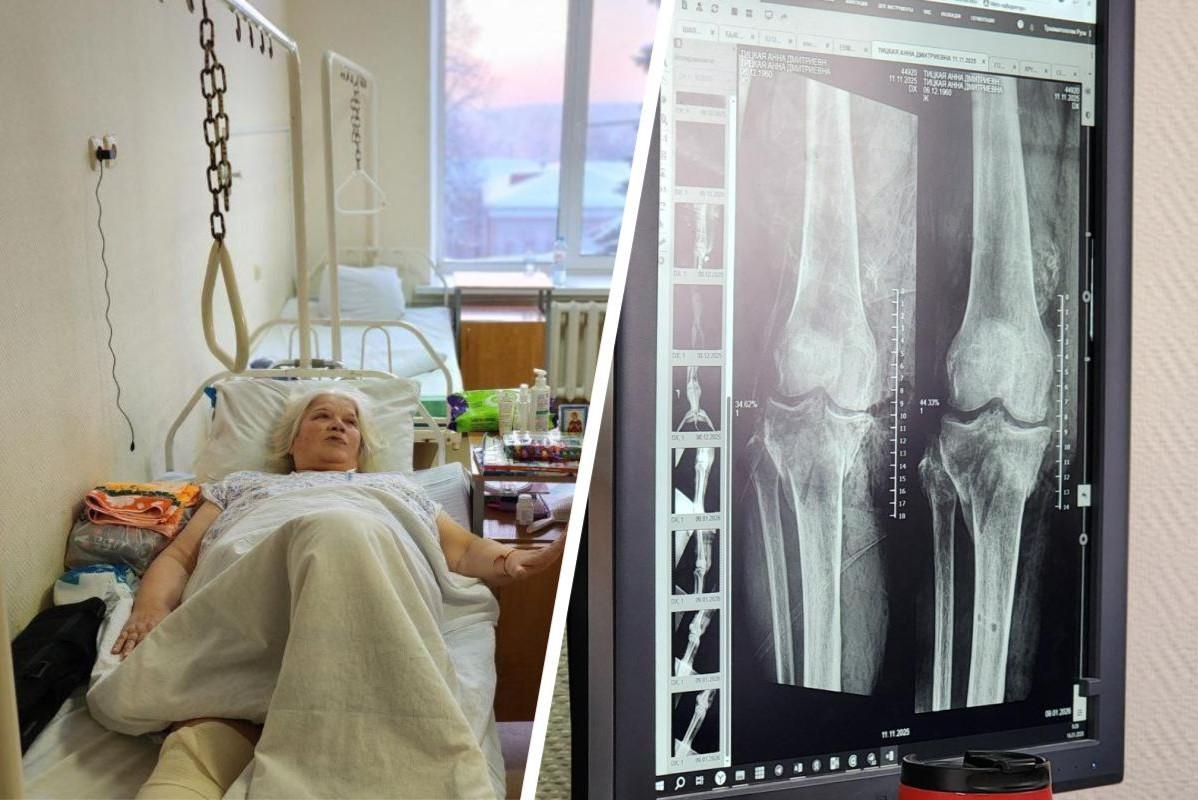

«Реанимировали на земле». Подробности состояния пенсионерки, на которую наехал 13-летний школьник на багги в ПодмосковьеВрачи спасли ногу жертве резонансного ДТП